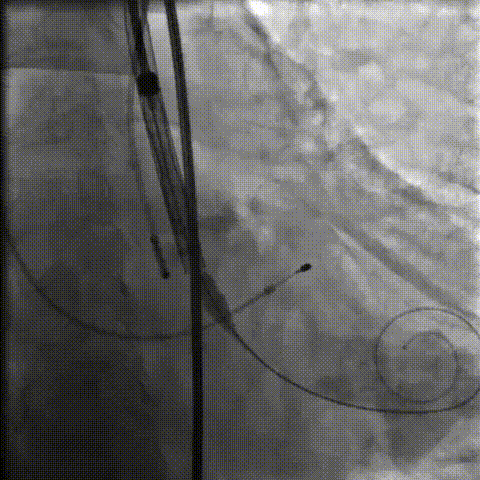

手术影像记录

主动脉根部造影

18mm球囊预扩

过弓、跨瓣

零位定位

工作位造影

缓慢脱钩

23mm球囊后扩

后扩后造影:无漏